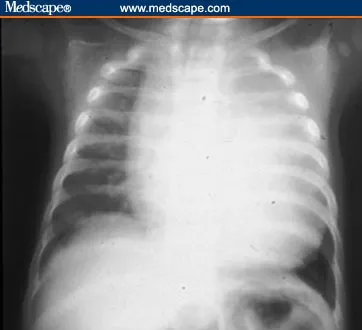

- Key: Massive cardiomegaly, profound hypotonia, hepatomegaly. "Floppy infant".